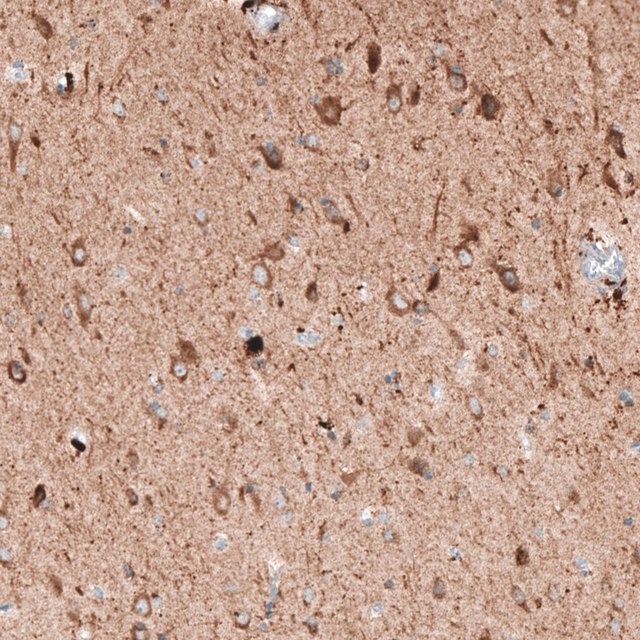

All Prestige Antibodies Powered by Atlas Antibodies are developed and validated by the Human Protein Atlas (HPA) project (www.proteinatlas.org)and as a result, are supported by the most extensive characterization in the industry. The Human Protein Atlas project can be subdivided into three efforts: Human Tissue Atlas, Cancer Atlas, and Human Cell Atlas. The antibodies that have been generated in support of the Tissue and Cancer Atlas projects have been tested by immunohistochemistry against hundreds of normal and disease tissues and through the recent efforts of the Human Cell Atlas project, many have been characterized by immunofluorescence to map the human proteome not only at the tissue level but now at the subcellular level. These images and the collection of this vast data set can be viewed on the Human Protein Atlas (HPA) site by clicking on the Image Gallery link. To view these protocols and other useful information about Prestige Antibodies and the HPA, visit sigma.com/prestige.

- IHC tissue array of 44 normal human tissues and 20 of the most common cancer type tissues.